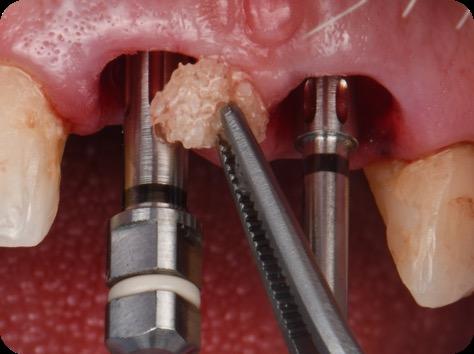

10. Titanium temporary abutments installed and composite bone graft of iPRF and MinerOss corticocancellous allograft added.

Fig 7. Implants immediately after installation.

Fig 8. Scanbody installation for custom abutment and definite restoration fabrication.

Fig 9. Periapical radiograph for verification of proper seating of the scanbodies.

Fig

Fig 11. Bone graft filling the horizontal gap between socket and implants.

Fig 12. Screw-retained provisional restoration placed into implants, with LPRF placed to protect graft material.